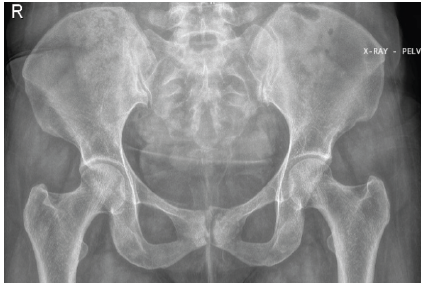

At follow-up, the patient demonstrated sustained clinical improvement with complete resolution of fever and significant recovery of mobility. At the last follow-up visit (3 months), plain radiographs of the pelvis showed no progression of bony destruction and features consistent with healing osteomyelitis (Fig. 7).

Figure 7: Anteroposterior radiograph of the pelvis at follow-up showing preserved pelvic alignment with no evidence of progressive bony destruction of the pubic symphysis or adjacent pubic rami. Findings are consistent with radiological stability/healing following combined anti-tubercular and anti-staphylococcal therapy.